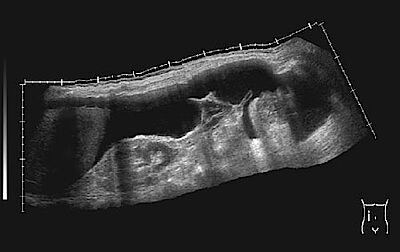

Kleine Wasseransammlungen, die lediglich bei einer Ultraschalluntersuchung auffallen und sich nicht verändern, müssen nicht therapiert werden. Jeder klinisch bereits sichtbare und jeder zunehmende Aszites ist behandlungsbedürftig.

Unter Ultraschallsicht wird an einer geeigneten Stelle punktiert. So können mehrere Liter (bis 20 l) Aszites auf einmal entfernt werden. Damit der Kreislauf durch den raschen Flüssigkeitsverlust nicht belastet wird, muss gleichzeitig eine konzentrierte Eiweißlösung infundiert werden.